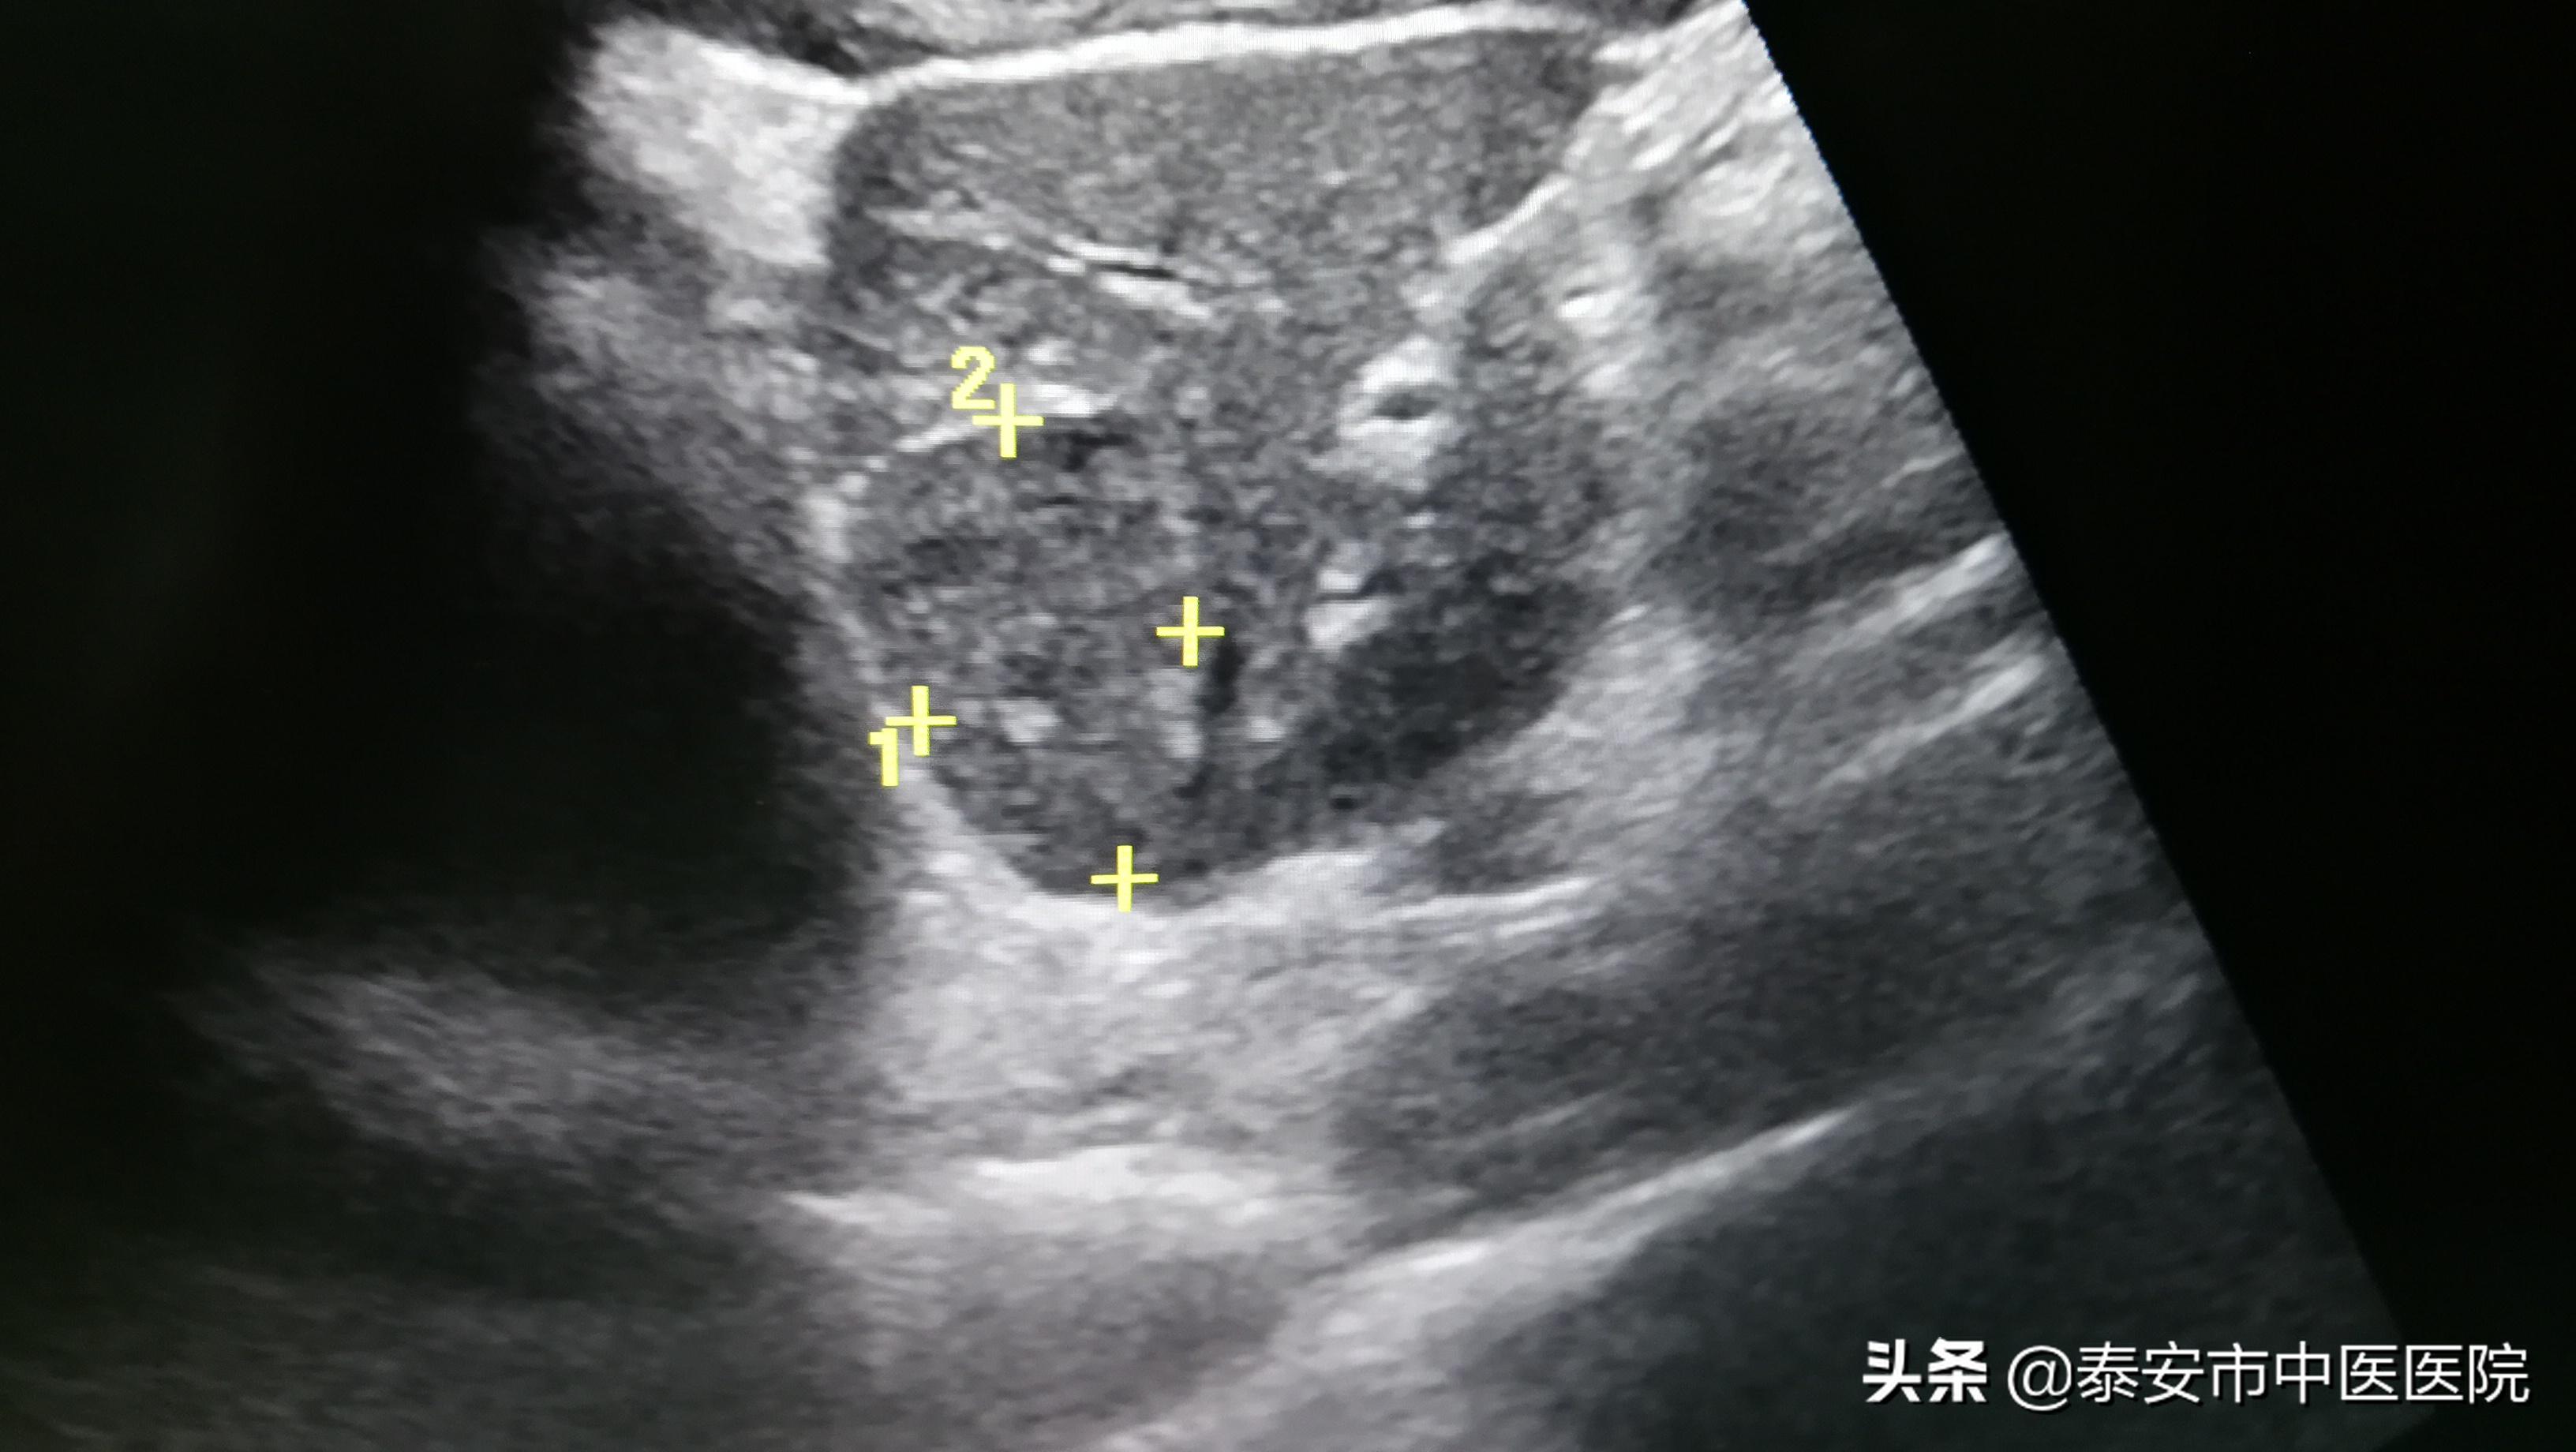

血管瘤消融前

50岁的李先生,是一位肝血管瘤患者,位于肝左叶,虽没有明显不适,但近两年来,三次行超声检查,发现血管瘤有明显增大的趋势,直径达到6.2厘米。李先生曾辗转于多家医院,均告知需要手术切除。李先生感到焦虑多时,经好友介绍并多渠道查询,得知*安泰**市中医医院超声介入科已开展多项超声引导下肿瘤消融治疗,微创无辐射,最为重要的是疗效与外科手术相当,于是前来就诊。